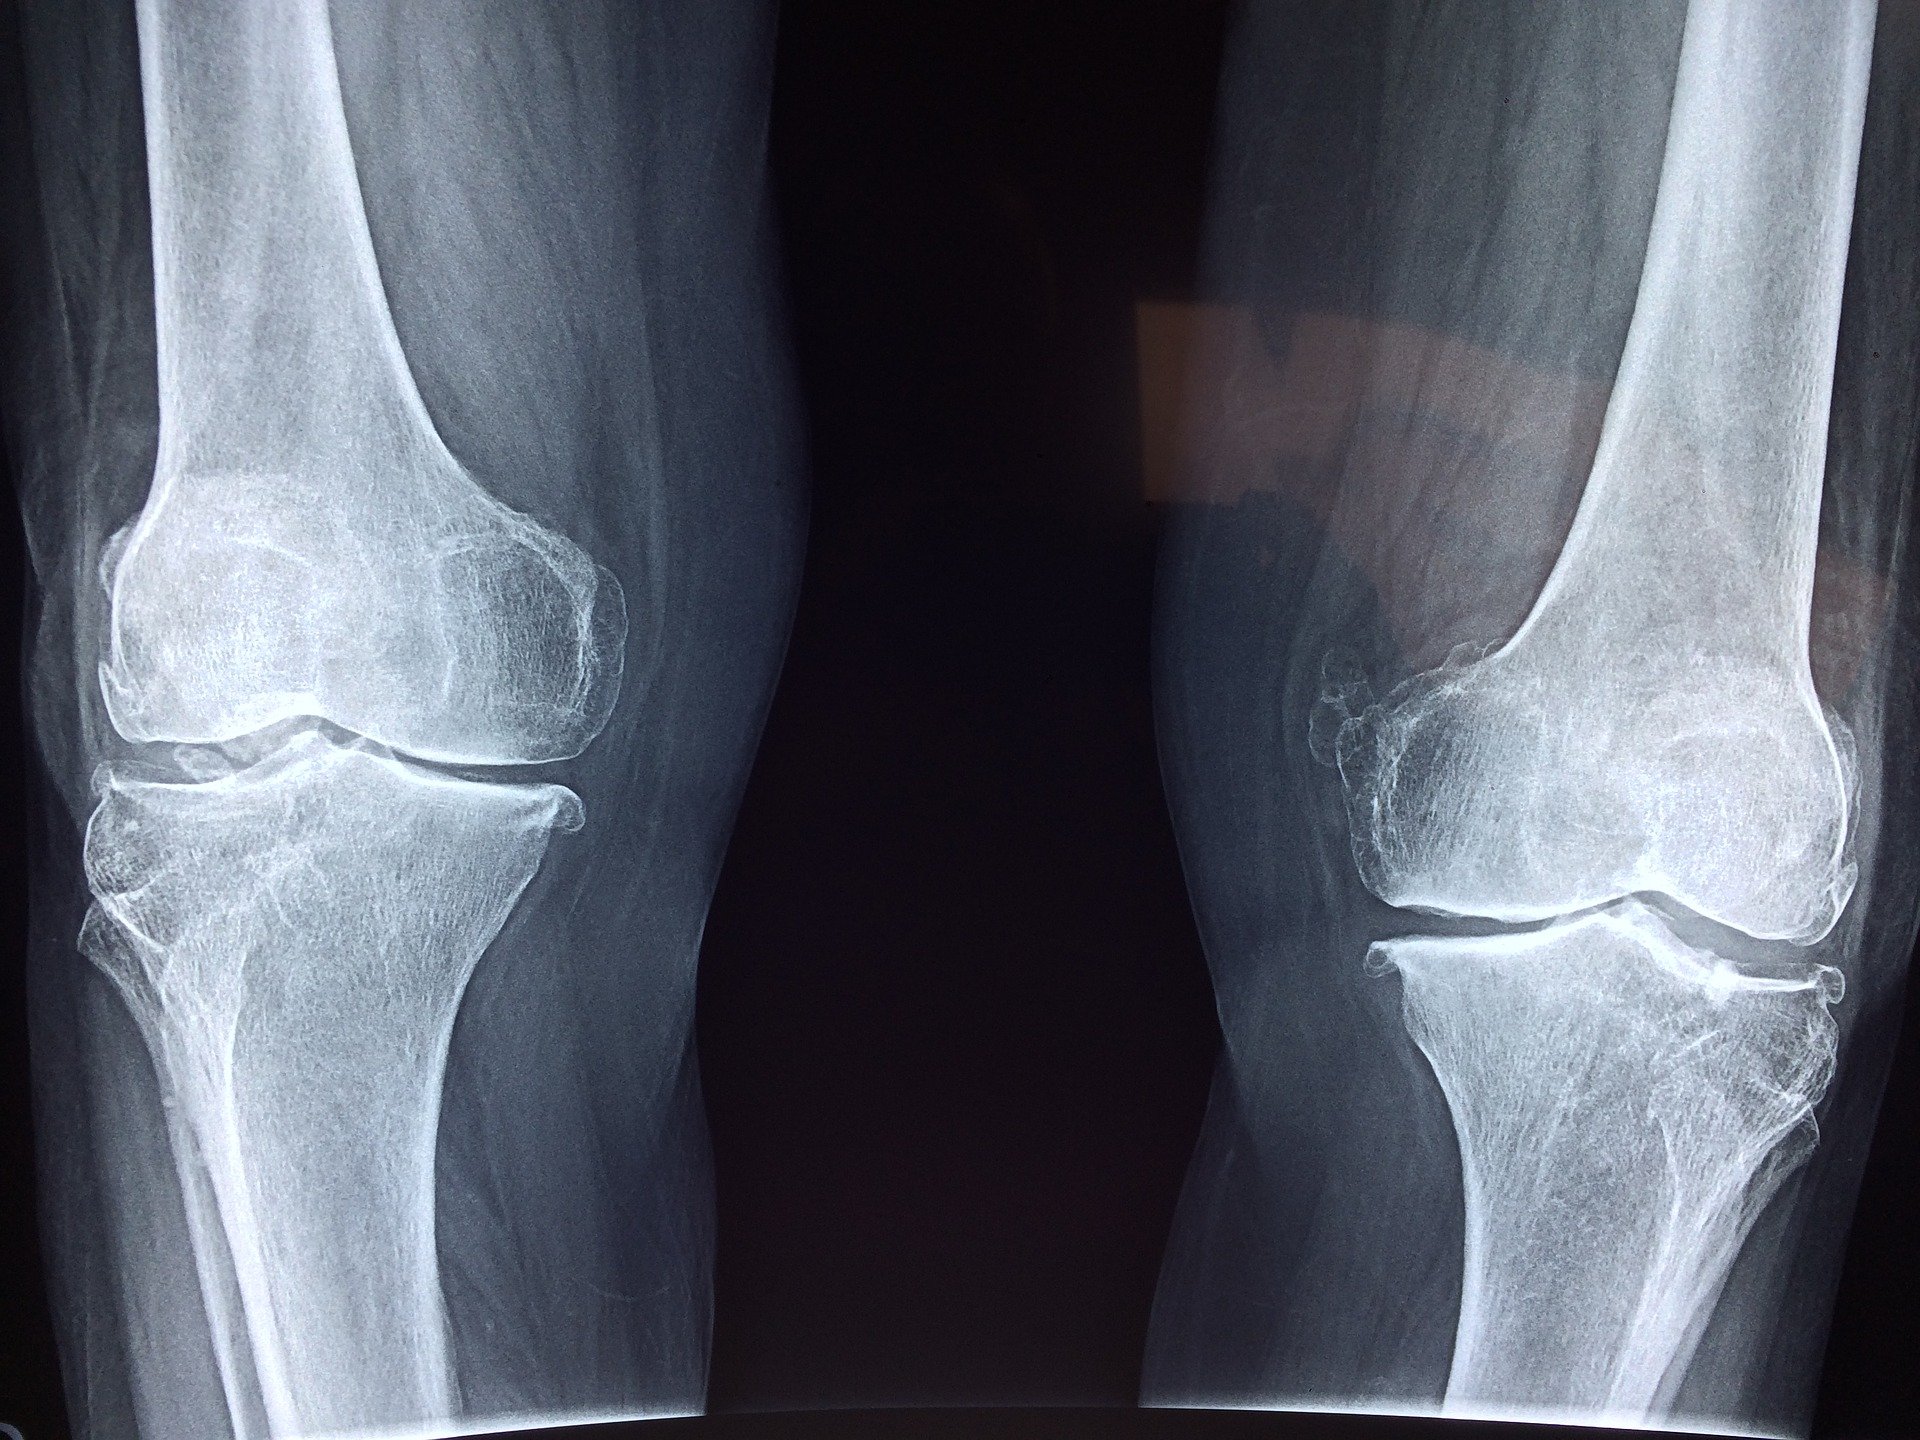

Powszechnie wiadomo, że ból i opuchlizna kolana mogą wskazywać na poważny problem. Jeśli objawy nasilają się, ważne jest, aby niezwłocznie skonsultować się z lekarzem. Przed wizytą u lekarza można zmniejszyć objawy w domu. Oto lista domowych sposobów na zmniejszenie obrzęku, bólu i wody w kolanie. Najlepszym rozwiązaniem jest jednak wizyta u lekarza.